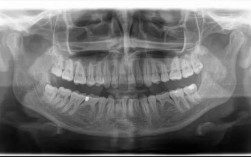

- 病例报告:选择1-2例自己参与处理的正畸病例(如牙列不齐、深覆颌),包含初诊资料(口内照、X线片、模型)、诊断、治疗方案、治疗过程及结果分析,体现临床思维。